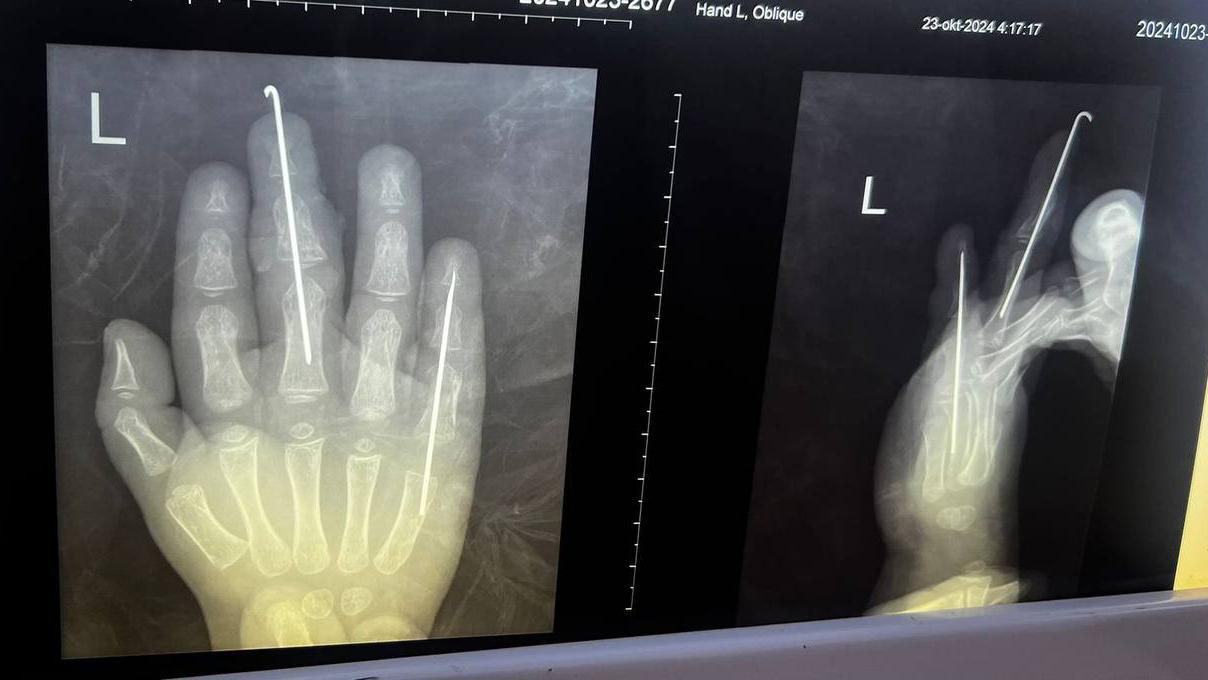

Врачи диагностировали у него открытый перелом двух пальцев со смещением. Специалисты прооперировали мальчика. Операция длилась почти четыре часа. Медикам удалось восстановить пальцы ребёнку. Кровоснабжение повреждённых тканей удовлетворительное — это значит, что они жизнеспособны. Сейчас его состояние стабильно.